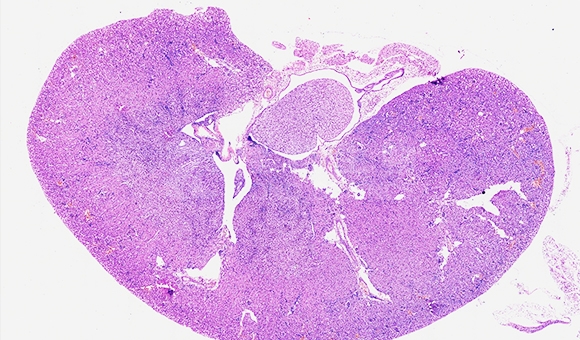

石蜡切片染色是组织学和病理学中的重要技术,它涉及将组织样本制成薄片,并通过特定的染料进行染色,以便在显微镜下观察细胞和组织的结构。

石蜡切片染色是一种在组织学和病理学中常用的技术,它涉及将组织样本制成薄片,并通过特定的染料进行染色,以便在显微镜下观察细胞和组织的结构。这个过程包括几个关键步骤:组织的固定、脱水、透明、浸蜡、切片、染色和封片。染色后的切片可以显示细胞内不同的细胞器及内含物以及不同类型的细胞组织,对于诊断疾病、研究细胞和组织的结构以及进行科学研究都非常重要。

9.染色:常用的染色方法包括苏木精-伊红染色(HE染色),其中细胞核被苏木精染成蓝紫色,细胞质被伊红染成粉红色。

病理学诊断:石蜡切片染色用于观察组织样本,帮助医生诊断癌症、炎症和其他疾病。

肿瘤研究:通过染色后的切片,可以观察肿瘤细胞的形态和生长模式,从而更好地理解肿瘤的生物学行为。

实验结果展示